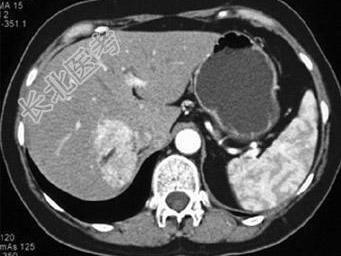

- 单项选择题中年患者,女性, 偶然发现肝团块,结合图像, 最可能的诊断是 ( )

A、肝癌

B、肝血管平滑肌脂肪瘤

C、局灶性结节增生

D、肝腺瘤

E、转移癌